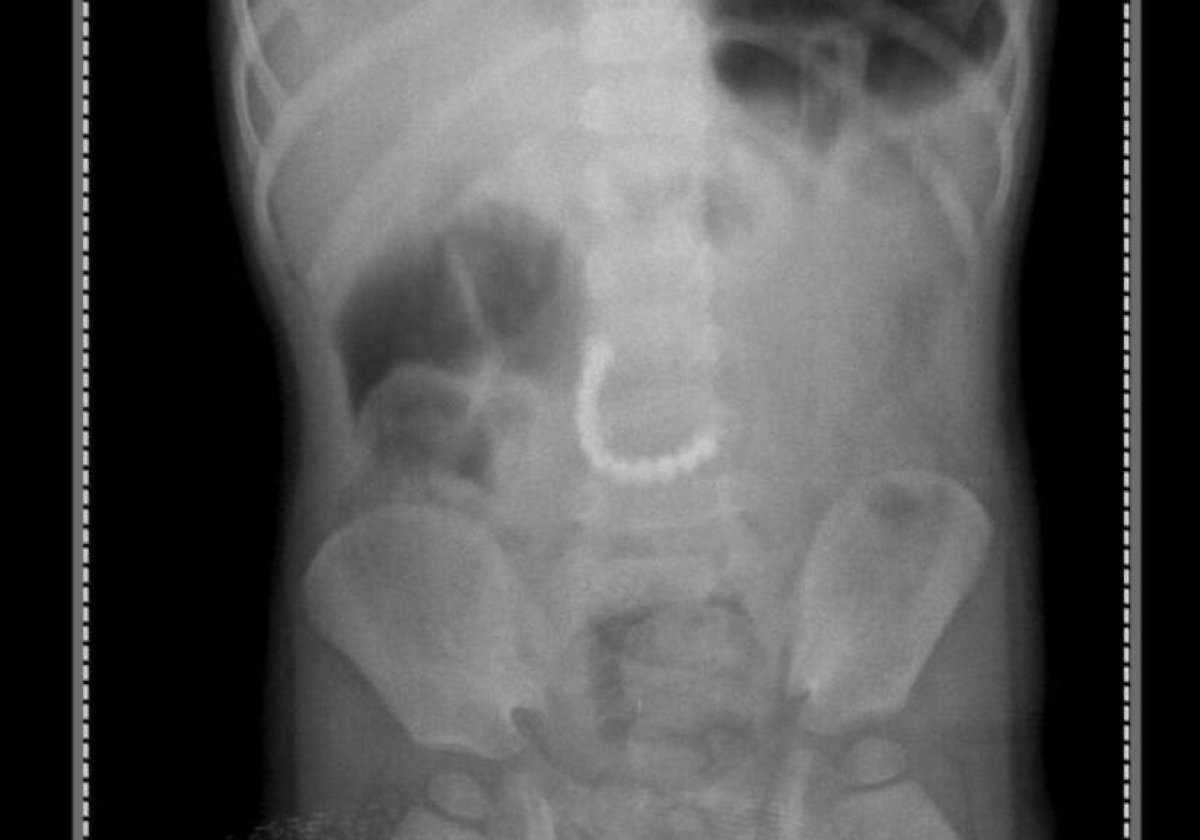

Как рассказали медики, у ребенка были сильные боли в животе, его рвало. Рентгенография органов брюшной полости показала наличие инородных тел в желудочно-кишечном тракте. Как позже выяснилось, это были магнитные детали от детских игрушек, 11 мелких шариков.